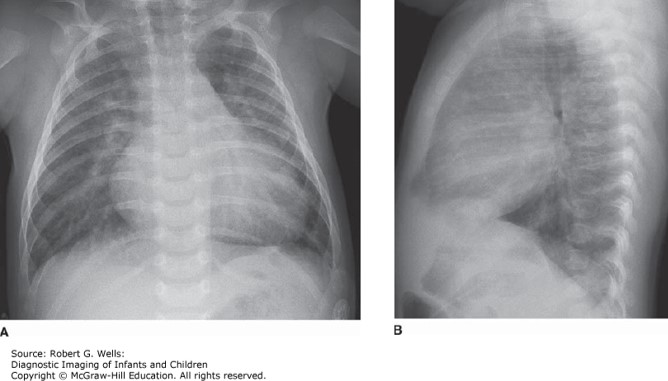

Photo: Wells RG. Diagnostic Imaging of Infants and Children; 2015.